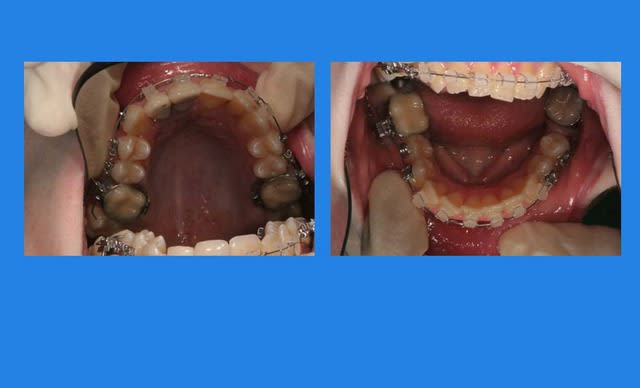

4mois après, comme ça n’avance pas vite, pose Q.H

et pose du mat. Inf.

2 wqai8e - Eugenol

contrôle 3 semaines après

3 m607iq - Eugenol

Puis elle ne vient pas pendant plus de 2 mois

et, oh surprise (mauvaise)

c’est la cata !!!

4 pzmuzx - Eugenol

Images 1 qtgoxf - Eugenol